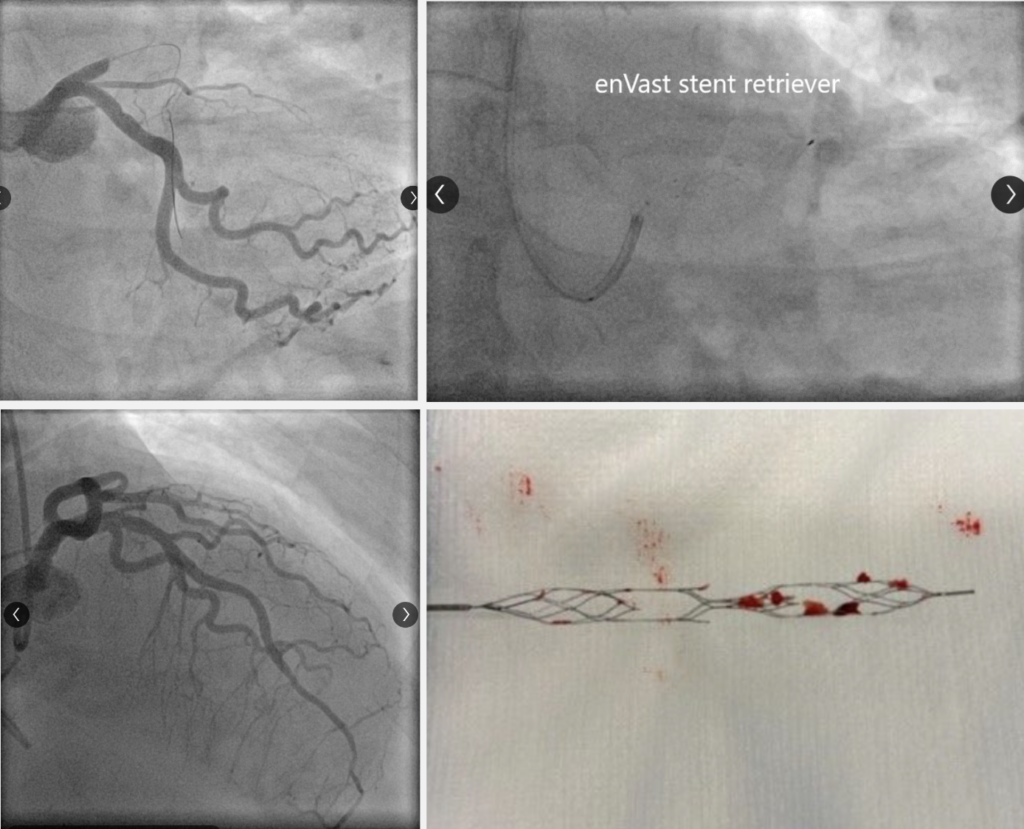

• After several attempts with balloon dilation and conventional thrombectomy, the decision was made to use the enVast* stent system:

• Two BMW guidewires were positioned in the posterior descending and posterolateral arteries (PDA and PLA), and the guidewire in the PDA was used to advance a microcatheter (MC) to the crux

• Through the MC, enVast* was introduced, after which the MC was withdrawn (Figure 2, Video 2 in the supplementary material)

• Continuous aspiration was then applied using a guide catheter extension connected to three overlock syringes to retrieve the enVast stent en bloc

• This maneuver resulted in the extraction of macroscopic thrombotic material and allowed visualization of vessel reopening (Figure 3, Video 3 in the supplementary material)

• The procedure was subsequently completed with the implantation of two drug-eluting stents (3.0 × 38 mm and 4.0 × 38 mm), achieving a final thrombolysis in myocardial infarction (TIMI) grade 3 flow (Video 4 in the supplementary material).

After failure of multiple attempts with balloon dilation and conventional thrombectomy techniques, the decision was made to employ the enVast system (NeVa, Vesalio, United States) as an alternative approach.

Two BMW guidewires were strategically placed at the posterior and posterolateral descending arteries. The posterior descending artery guidewire facilitated the insertion of a microcatheter up to the occlusion site. Subsequently, enVast was navigated through the microcatheter, which was then removed. To ensure continuous aspiration during retrieval, a guide catheter extension, equipped with three luerlock syringes, was utilized. This meticulous process with enVast effectively removed macroscopic thrombotic material and allowed for the visualization of the artery’s opening. The procedure was concluded with the implantation of two stents.